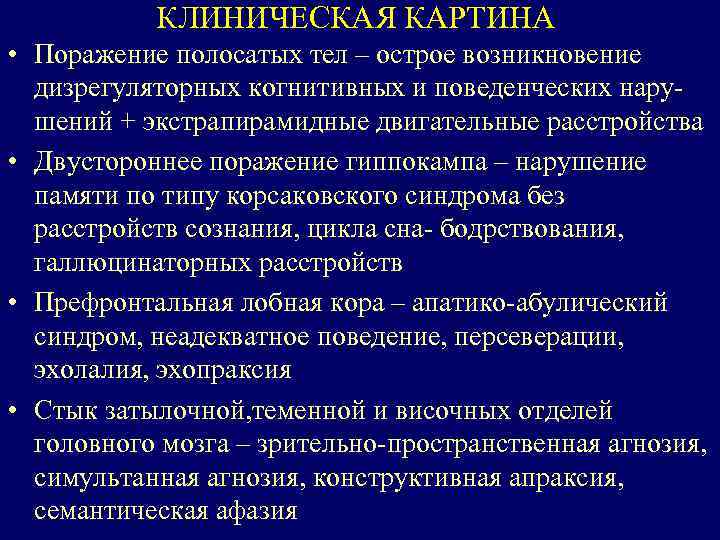

КЛИНИЧЕСКАЯ КАРТИНА • Поражение полосатых тел – острое возникновение дизрегуляторных когнитивных и поведенческих нарушений + экстрапирамидные двигательные расстройства • Двустороннее поражение гиппокампа – нарушение памяти по типу корсаковского синдрома без расстройств сознания, цикла сна- бодрствования, галлюцинаторных расстройств • Префронтальная лобная кора – апатико-абулический синдром, неадекватное поведение, персеверации, эхолалия, эхопраксия • Стык затылочной, теменной и височных отделей головного мозга – зрительно-пространственная агнозия, симультанная агнозия, конструктивная апраксия, семантическая афазия